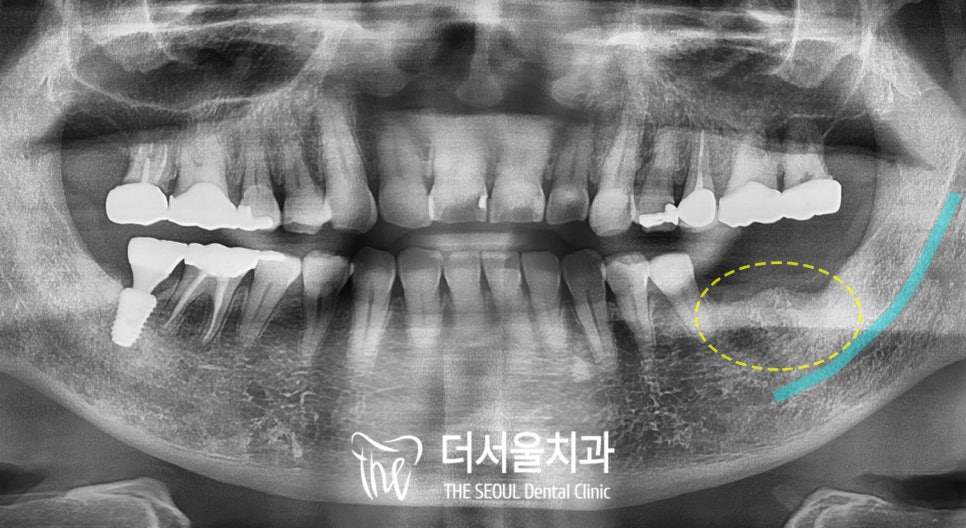

그래서 엑스레이를 찍어서 확인해 보니

#36의 치아 뿌리 일부가 잇몸뼈 안에

남아있던 상태였습니다.

그래서

#36 잔존 치근 발거 후

#36=37 디지털 임플란트 로

구치부를 재건해 드리기로 했습니다.